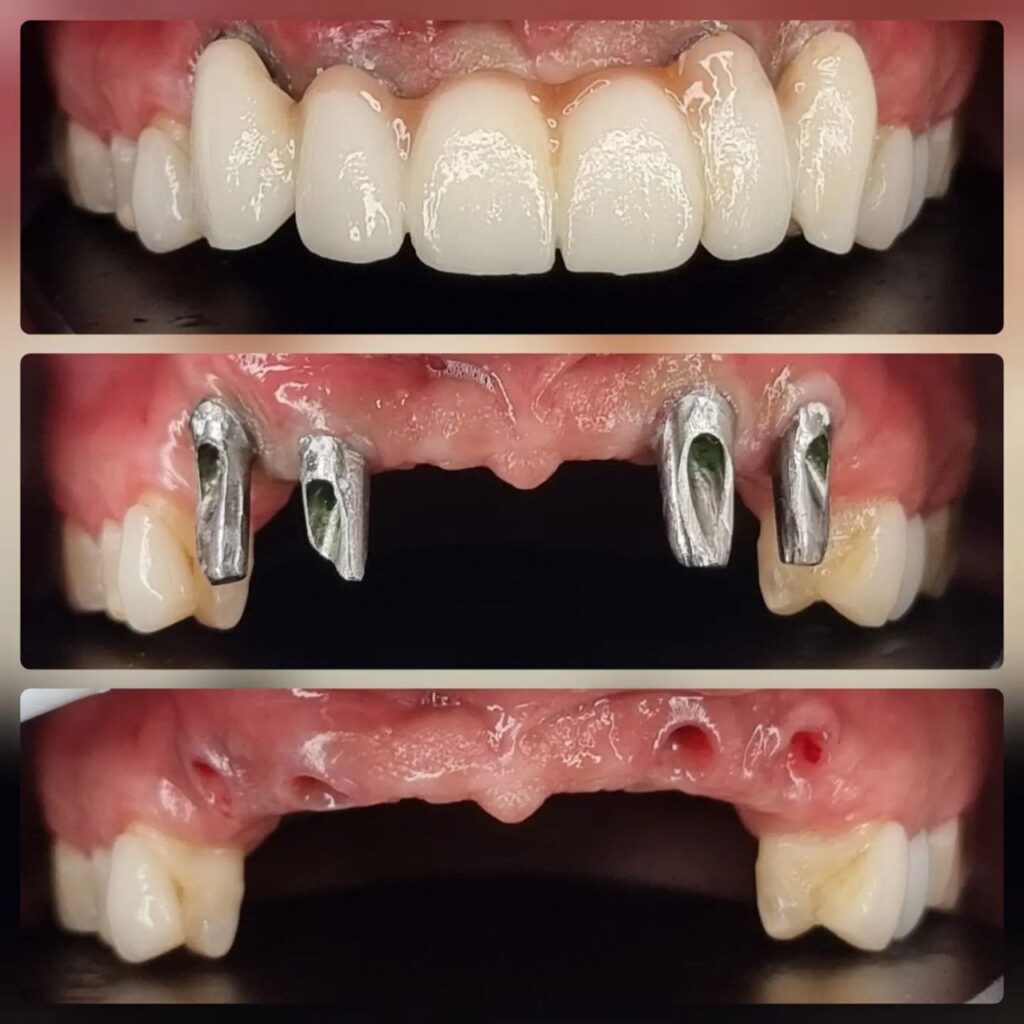

کاشت ایمپلنت دندان

اطمینان حاصل کردن از اینکه دندانهایتان به نحوی زیبا و طبیعی جایگزین شدهاند، از اهمیت بسیاری برخوردار است. ایمپلنت دندان به عنوان یک روش درمانی دائمی در دندانپزشکی شناخته میشود که حاصل آن، یک دندان زیبا و طبیعی در دهان شما خواهد بود.

هرچند که این روش درمانی هزینهی بیشتری نسبت به روشهای دیگر دارد، اما ارزش زیبایی که ایجاد میکند، قابل انکار نیست. ایمپلنتها به قدری شبیه به دندانهای طبیعی هستند که به سختی میتوان آنها را از دیگر دندانها تشخیص داد.